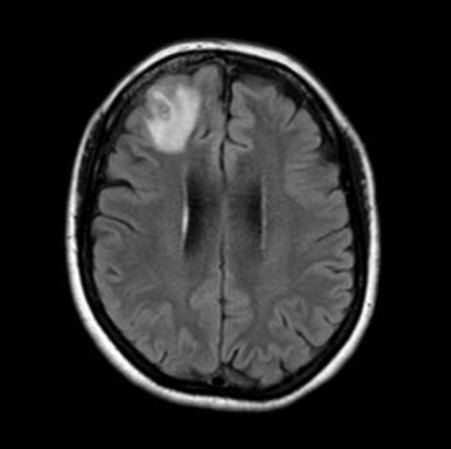

Three weeks later, the woman was in the hospital with a fever and cough. CT scans revealed a clue that was telling, in retrospect: Some of her lung lesions appeared to be migrating. A second clue came months later, when the woman became forgetful and depressed. “She had a very astute GP who thought, ‘Something’s not right here, I better do an MRI of the brain,’” says Sanjaya Senanayake, an infectious disease physician at the Australian National University and the Canberra Hospital.

That brain scan turned up a ghostly glow in her frontal lobe. It could have been cancer, an abscess or another affliction, Senanayake says. “No one thought it was going to be a worm.”